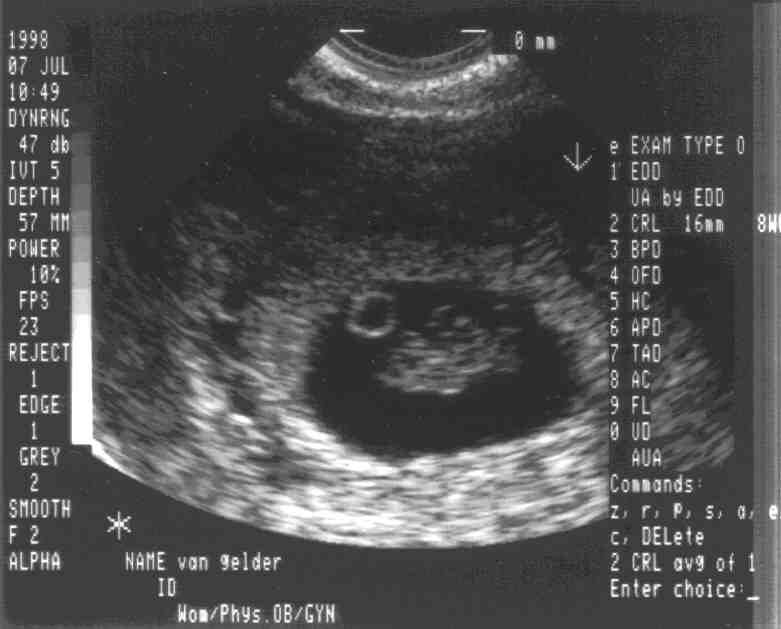

Peanut at 8 weeks

Two weeks later, you can see so much more. Do you see a resemblance to the father yet? Ok, you have to use your imagination a bit, but when the image was live, it all made more sense.

The thing that looks like a smoke ring in the dark area is the yolk sack. The head is down and to the right from the yolk sack. The arms are pointing up in the middle, and the legs are pointing up toward the right.

The big news at today's visit was that since everything looked great the risk of miscarriage has dropped to 2 percent. Whew!